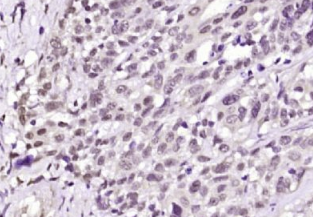

多聚甲醛固定,石蜡包埋(人结肠癌);用柠檬酸钠缓冲液(pH6.0)煮沸15min后获得抗原;用3%过氧化氢阻断内源过氧化物酶20分钟;阻断缓冲液(正常山羊血清)37℃30min;抗体(ACK1)多克隆抗体在1:200孵育。在4°C下过夜,然后根据SP试剂盒(兔子)说明和DAB染色进行操作。